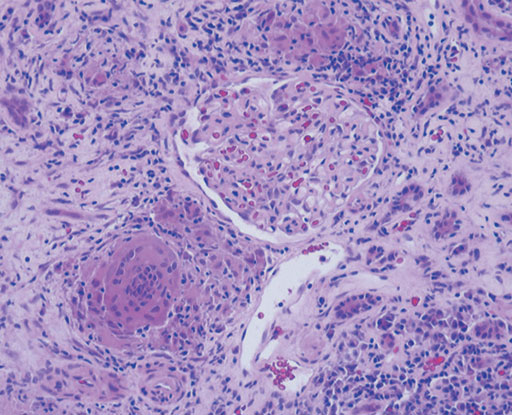

Sarcoidosisは通常,縦隔および両側肺門部の腫大をともなって発症するが,まれに皮膚,中枢神経,軟部腫瘍で発症することがある.腎病変は,高カルシウム血症にともなう腎結石や腎障害がみられるのが一般的であるが,まれに多発性のnoduleを形成することが知られている.腎臓の多発性結節の鑑別としては,von Hippel-Lindau病に認められる腎癌,転移性腎腫瘍,悪性リンパ腫,結核等の感染症,腎盂腎炎が鑑別に上がる.今回の症例では筋肉内に比較的,均一に造影される結節が認められることからsarcoidosisの診断が示唆される.転移性腫瘍は通常,内部に壊死を伴って不均一に造影される.悪性リンパ腫ではdiffuseな筋肉の腫大を呈することが多い.Sarcoidosisの筋病変は単発性または多発性の結節を呈するnodular typeとmyopathic typeが知られている.結節型はMRIでは,T1強調像,T2強調像,造影T1強調像のいずれのsequenceにおいても中心部に不規則な星ぼう状の低信号(dark star sign)を呈するのが特徴的である.Myopathic typeではMRIでは異常信号として捉えにくいが,67Gaシンチでは筋肉に沿って瀰漫性の集積が認められる.実際の症例では皮膚,腎臓,筋肉いずれの病変からもbiopsyによりsarcoidosisの診断が得られている.腎臓の病理では系球体周囲に非乾酪性肉芽腫の形成を認め,また一部に巨細胞も認める.

• 図4 HE染色(×200)